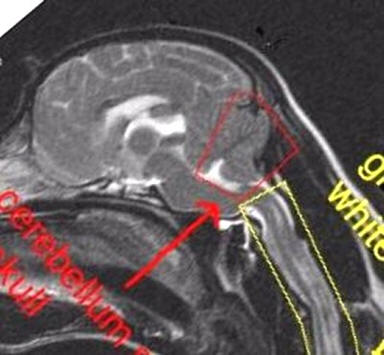

Age Unknown

No symptoms of SM

Mild to Moderate Malformation, cerebellum

moderately squashed

Herniation of cerebellum

Medulla squashed/kinked

No syrinxes

Moderate Malformation, cerebellum